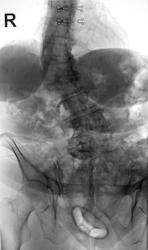

В малом тазу гинекологически пессарий (вроде так пишется??), только слишком низко кажется. Сколиоз где-то 3-4 степени.

Вы правы уважаемая коллега.

Нет это старое, и не противозачаточное средство, при выпадениях влагалища давно используется.